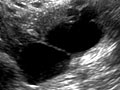

A pelvic ultrasound uses sound waves to make a picture of the organs and structures in the lower belly (pelvis).

Organs and structures that are solid and uniform (such as the uterus, ovaries, or prostate gland) or that are fluid-filled (such as the bladder) show up clearly on a pelvic ultrasound. Bones may block other organs from being seen. Air-filled organs, such as the intestines, can make the image less clear.

In all three types of pelvic ultrasound, the transducer sends the reflected sound waves to a computer, which makes them into a picture that is shown on a video screen. Ultrasound pictures or videos may be saved as a permanent record.